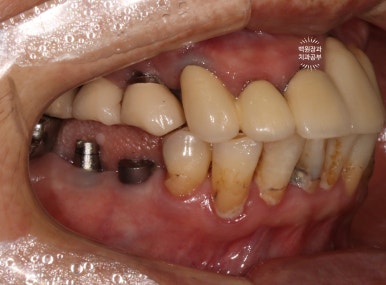

보시면 이가 없던 자리에 임플란트 두개가 생겨 있는 것을 보실 수 있습니다.

발치 동시 임플란트의 또 다른 특징으로, 대부분 임플란트 2차수술을 하지 않습니다.

왜냐~ 이를 뽑으면서 임플란트를 바로 심기 때문에, 잇몸이 비어있는 부분이 있잖아요? ㅎㅎ 그러니 당연히 뚜껑을 껴야한다구요!! 그래서 임플란트 수술이 모두 끝나버립니다.

오른쪽 아래 작은어금니에 스트라우만 임플란트를 심고 골이식을 했습니다.

이를 뽑으면서 동시에 임플란트를 심는 발치 즉시 임플란트의 경우, 뼈이식이 필수적으로 동반될 수밖에 없습니다.